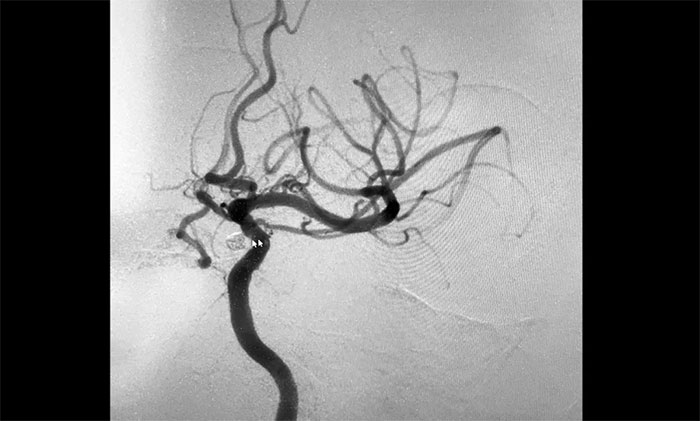

▲ 術(shù)后,成功栓塞動脈瘤并開通血管

術(shù)中,席剛明教授在王貴平博士及醫(yī)護(hù)團(tuán)隊密切配合下,先對左頸內(nèi)動脈C6段動脈瘤進(jìn)行彈簧圈栓塞治療,經(jīng)Echelon-10微導(dǎo)管送入彈簧圈,成籃滿意后暫不解脫;隨后,微導(dǎo)絲引導(dǎo)球囊擴(kuò)張導(dǎo)管頭端置于左側(cè)大腦中動脈M1段,球囊部分覆蓋左頸內(nèi)動脈C6狹窄段,進(jìn)行球囊擴(kuò)張,擴(kuò)張后見左頸內(nèi)動脈C6段狹窄明顯改善,隨后釋放支架于左頸內(nèi)動脈C7段至C4段,造影見左頸內(nèi)動脈、左大腦中動脈、左大腦前動脈顯影可。最后,繼續(xù)栓塞動脈瘤,經(jīng)Echelon-10微導(dǎo)管送入多枚彈簧圈,填塞滿意后解脫,造影見動脈瘤基本不顯影;復(fù)查造影,行3D造影見左頸內(nèi)動脈、左大腦中動脈、左大腦前動脈顯影可;行支架CT見支架成形滿意,行XperCT未見顱內(nèi)出血,手術(shù)圓滿完成。